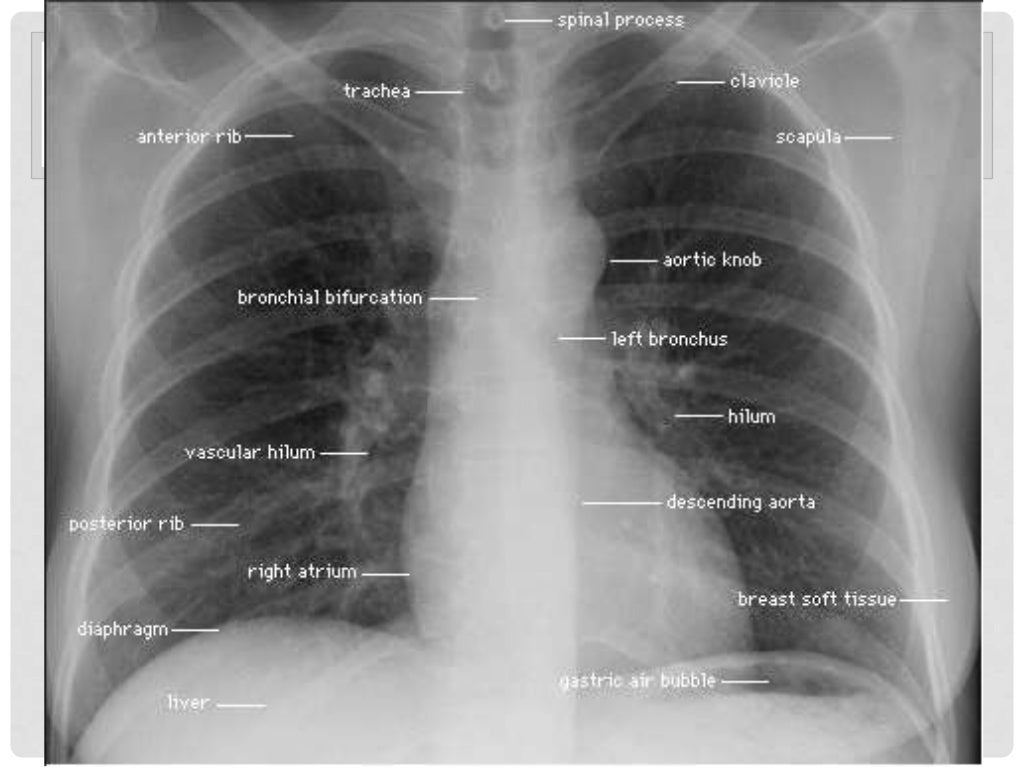

Normal Chest Xray PA View Health Insurance Quotes Nurse Radiology

Normal Chest Xray PA View Health Insurance Quotes Nurse Radiology

Normal Chest X ray

Normal Chest X ray

Anatomy Of Chest X Ray Normal Chest Xray Stock Photo Download Image

Anatomy Of Chest X Ray Normal Chest Xray Stock Photo Download Image